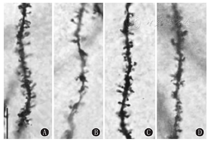

生理盐水对照组、ICG-001对照组、VPA组和ICG-001处理组海马CA1区锥体细胞树突棘密度比较差异有统计学意义(P<0.05)。与生理盐水对照组相比,VPA组大鼠CA1区顶树突棘密度显著降低(P<0.05),ICG-001处理组CA1区顶树突棘密度增加(P<0.05),接近于生理盐水对照组水平(P>0.05)(表3,图2)。

注:VPA:丙戊酸钠 VPA:Sodium valproate

与生理盐水对照组相比,VPA组海马CA1区锥体细胞蘑菇型顶树突棘减少(P<0.05),ICG-001处理组海马CA1区锥体细胞蘑菇型顶树突棘增多(P<0.05),接近于生理盐水对照组水平(P>0.05)。与生理盐水对照组相比,VPA组大鼠海马CA1区锥体细胞顶瘦长型树突棘增多(P<0.05),ICG-001处理组海马CA1区锥体细胞瘦长型顶树突棘减少(P<0.05),接近于生理盐水对照组水平(P>0.05)。VPA组与ICG-001处理组短粗型顶树突棘比较,差异无统计学意义(P>0.05)。VPA组与ICG-001处理组丝状伪足顶树突棘比较,差异无统计学意义(P>0.05)(表3,图2)。

海马树突棘密度和形态异常与孤独症症状密切相关[3,14]。本研究结果证实,VPA诱导的孤独症大鼠CA1区锥体细胞顶树突棘密度降低,与文献报道一致[4],ICG-001使孤独症大鼠海马顶树突棘密度增加。瘦长型与丝状伪足型树突棘为不成熟型,蘑菇型与短粗型树突棘为成熟状态。本研究结果表明,VPA组大鼠海马CA1区锥体细胞蘑菇型顶树突棘减少和顶瘦长型树突棘增多,与文献报道一致[15];ICG-001使孤独症大鼠海马锥体细胞蘑菇型顶树突棘增多和长型顶树突棘减少。这表明ICG-001能够促进孤独症大鼠树突棘形态发育。